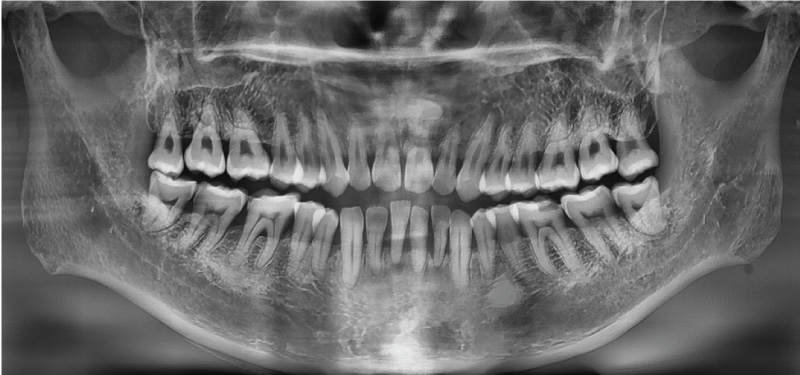

Vatech A9 обеспечивает высококачественные панорамные изображения, выполненные с помощью функции Magic Pan, что повышает точность диагностики и улучшает планирование лечения.

Анатомическая зона сканирования 10х8 см

Зона сканирования 10х8 см предоставляет необходимую диагностику при планировании лечения зубов верхней и нижней челюсти